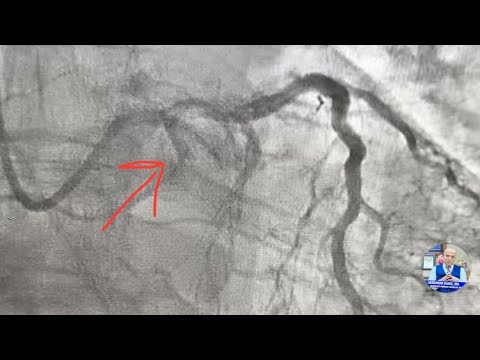

A complex Complicated CTO LCX! IVL lithotripsy and PCI . Step by step !

PCI Of Heavy Calcified RCA Using IVL

CTO RCA- IVL Lithotripsy shockwave, step by step !